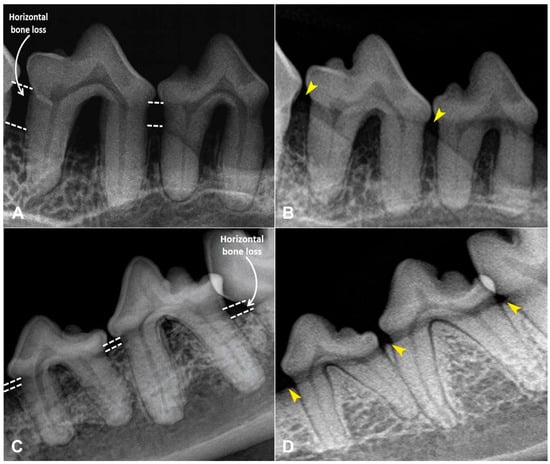

Clinical Evaluation of Autologous PRP (Platelet-Rich Plasma) in the Treatment of Periodontitis in Small-Breed Dogs

Periodontal disease is a progressive inflammatory condition frequently diagnosed in dogs, particularly in small breeds such as Yorkshire Terriers, Toy Terriers, Spitz, Toy Poodles and other breeds predisposed to rapid plaque and tartar accumulation. As the field of regenerative medicine becomes more popular, [...] Read more.

Periodontal disease is a progressive inflammatory condition frequently diagnosed in dogs, particularly in small breeds such as Yorkshire Terriers, Toy Terriers, Spitz, Toy Poodles and other breeds predisposed to rapid plaque and tartar accumulation. As the field of regenerative medicine becomes more popular, more and more attention is being paid to substances that promote tissue regeneration, one of which is platelet-rich plasma (PRP). PRP is an autologous blood-derived product rich in growth factors that stimulate tissue regeneration and modulate inflammation. This study aimed to evaluate the clinical effectiveness of PRP injections without additional activating agents in the management of stage 2–3 periodontitis in small-breed dogs. Forty-two adult dogs (Yorkshire Terriers, Toy Terriers, Pomeranians, Toy Poodles, and Havanese) were enrolled and divided into two groups: PRP (n = 30) and control (n = 12). Following standard dental prophylaxis, the PRP group received gingival, submucosal, and periodontal pocket injections of PRP (0.1 mL per site). Periodontitis stage, gingival index, periodontal pocket depth, and horizontal bone loss were evaluated at baseline and 30 days post-treatment. PRP therapy significantly improved all evaluated parameters (p < 0.05). The gingival index decreased threefold, periodontal pocket depth was reduced twofold, and horizontal bone loss decreased by more than twofold compared with baseline and controls. No adverse reactions, discomfort, or postoperative complications were observed. The administration of non-activated PRP as an adjunct to dental cleaning significantly enhances soft and hard tissue regeneration in small-breed dogs with stage 2–3 periodontitis. PRP therapy represents a safe, minimally invasive, and effective regenerative approach for improving periodontal health in routine veterinary dentistry. Full article